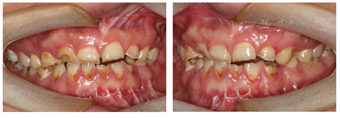

(1)面部检查:面部外形不对称,颏部居中,两侧口角高度不一致,面下1/3高度减小,两侧颧弓突度一致,下颌前突。中位笑线,上唇长度适中(图1)。(2)关节检查:颞颌关节:弹响(-),杂音(-),疼痛(-)。开口度正常,开口型有偏斜,肌肉触诊压痛:右侧上颌结节(+)、左侧上颌结节(++)、双侧翼内肌(+),其他肌肉及颞下颌关节区未诉异常,关节载荷实验无任何紧张和疼痛不适。(3)口内检查:上下颌牙中线较面中线向右偏斜,前后牙广泛不均匀磨耗,前牙磨耗后呈刃状;14、21、22、23及下颌牙唇颊侧颈部见釉质缺损,部分牙本质暴露,呈黄褐色,少量白垩色;44牙见开髓孔,表面暂封。12缺失,缺失牙间隙无。全口牙龈色形质未见异常,11牙、21牙唇侧牙龈龈缘高度不一致,21牙较11牙龈缘高约3mm。全口口腔卫生状况良好,菌斑、软垢少量,未及牙石及牙周袋。咬合检查:11-14牙与对颌牙反

,21牙与31、31牙对刃,左侧尖牙至前磨牙深覆盖,

曲线不平(图2,图3)。(4)影像学检查: